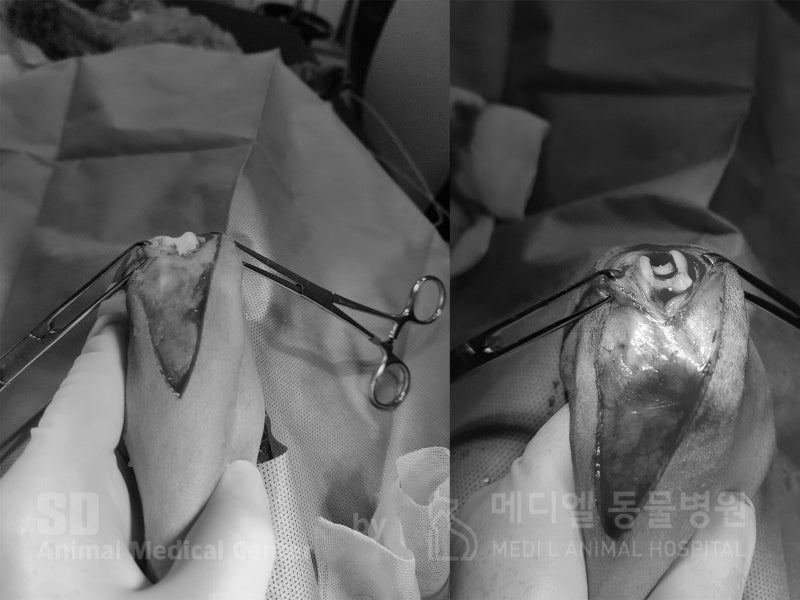

활차구 성형술으로, 활차구 고랑을 깊게 파주었습니다. (왼쪽)수술전, (오른쪽)수술후

슬개골 탈구 수술을 진행하였고, 더 이상 슬개골이 미끄러져 빠지지 않게 얕게 있던 고랑을 깊게 파주었습니다.

이 환자의 경우 활차구 성형,지대중첩과, 경골조면변위 방법으로 진행되었습니다.

수술 전 빠져있던 슬개골이 수술 직 후에 정상위치로 돌아와있습니다.